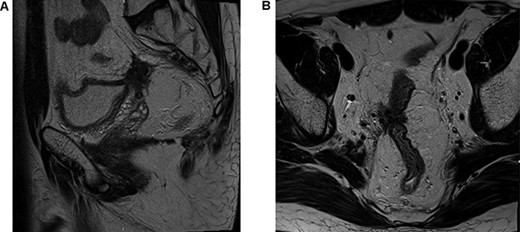

He proceeded to sigmoidoscopy, which identified a neoplasm in the upper one-third of the rectum with evidence of luminal compromise. Biopsy of this lesion at index sigmoidoscopy confirmed moderately differentiated adenocarcinoma. No synchronous tumors were identified on completion colonoscopy. Carcinoembryonic antigen (CEA) level at diagnosis was 106 ng/mL. MR staging T4BN2Mx tumor with suggestion of local bladder invasion and right pelvic side wall (Fig. 1). Computerised tomography Thorax, Abdomen and Pelvis (CTTAP) demonstrated no distant metastasis in the liver or lung but did demonstrate para-aortic lymphadenopathy. Considering the lymphadenopathy and following Multidisciplinary team (MDT) discussion, a PET CT scan was arranged, which showed these to be uninvolved but did demonstrate positive inferior mesenteric artery nodes.

T4BN2MX Upper rectal cancer (A) axial view and (B) sagittal view.